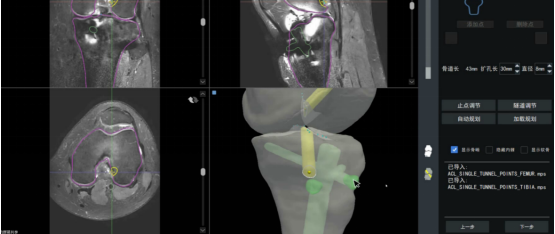

膝关节专科在膝关节伤病诊疗中,全面实现了数字化、个性化、智能化和精准微创。从患者住院的第一天到出院,就能在膝关节外科专家、康复科专家、内科专家、药剂科专家和手术相关的工程师(个性化全膝置换用人工关节定制工程师、算法工程师、导航工程师和机械工程师)的共同保驾护航下,可以高效完成专科的术前准备、内科的术前治疗、个性化康复方案的制定和数字化智慧化术前规划,使得每一台手术的术前,都可以依托患者损伤膝关节自己个性化三维仿真模型,经过手术团队和工程师们的术前反复讨论优化,无论是无需机器人辅助手术的手术还是需要机器人辅助的手术,都可以给术中精准操作提供帮助,更可以在精确导航下由机器人辅助完成手术。

患者在膝关节专科接受治疗时,享受到的是膝关节伤病诊断与治疗的全方位的智慧诊疗升级。从单纯顶尖专家的诊断到顶尖专家结合被训练成顶尖专家的水平的AI辅助诊断的结合,从标准手术治疗到个性化手术治疗的提升,再到住院时便开始针对手术所需医疗器械(如人工膝关节)的个性化定制,常规术前看片子讨论的术前准备也升级为数字化、智慧化的术前规划,手术过程页不仅仅仅只依赖医生经验,升级到有导航和机器人精准辅助,真正实现了伤病诊断和治疗全生命周期的数字化、个性化、智能化和精准微创的各个方面。

8. 膝关节手术机器人:目前日常膝关节专科手术基本全方位完成了数字化智慧型术前规划、术中精准导航和术中机器人精确手术。

个性化定制人工膝关节术前模拟手术

前交叉韧带第一次单束重建后没能重返运动且再断裂,机器人导航可以翻修成双束重建,术后再次重返运动(淡绿骨道是陈旧单束重建骨道,深绿和黄色骨道是新的双束重建骨道)